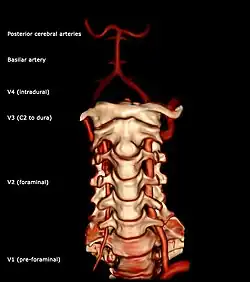

Segments of vertebral artery anterior projection

The vertebral artery may be divided into four parts:

The second (foraminal) part runs upward through the transverse foramina of the C6 to C2 vertebrae, and is surrounded by branches from the inferior cervical sympathetic ganglion and by a plexus of veins which unite to form the vertebral vein at the lower part of the neck. It is situated in front of the trunks of the cervical nerves, and pursues an almost vertical course as far as the transverse process of the axis.

The third (extradural or atlantic) part issues from the C2 foramen transversarium on the medial side of the Rectus capitis lateralis. It is further subdivided into the vertical part V3v passing vertically upwards, crossing the C2 root and entering the foramen transversarium of C1, and the horizontal part V3h, curving medially and posteriorly behind the superior articular process of the atlas, the anterior ramus of the first cervical nerve being on its medial side; it then lies in the groove on the upper surface of the posterior arch of the atlas, and enters the vertebral canal by passing beneath the posterior atlantoöccipital membrane. This part of the artery is covered by the Semispinalis capitis and is contained in the suboccipital triangle—a triangular space bounded by the Rectus capitis posterior major, the Obliquus superior, and the Obliquus inferior. The first cervical or suboccipital nerve lies between the artery and the posterior arch of the atlas.

Segments of vertebral artery lateral projectionThe fourth (intradural or intracranial) part pierces the dura mater and inclines medially to the front of the medulla oblongata; it is placed between the hypoglossal nerve and the anterior root of the first cervical nerve and beneath the first digitation of the ligamentum denticulatum. At the lower border of the pons, it unites with the vessel of the opposite side to form the basilar artery.